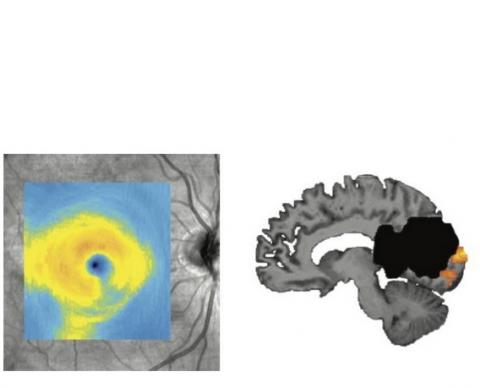

Le protocole de traitement comprendrait un test du champ visuel et un examen de la vue afin d'identifier la discordance entre le déficit visuel et la dégénérescence des cellules ganglionnaires de la rétine. Cela permettrait d’identifier les connexions intactes entre les yeux et le cerveau et d’utiliser ces données pour cibler les thérapies de rééducation visuelle sur les zones du champ de vision les plus susceptibles de récupérer. Ainsi, le visuel ci-dessous montre une dégénérescence de l'œil (visible sur le coin inférieur droit) après un AVC dans la zone de traitement visuel du cerveau (en noir sur visuel de droite).

Ce visuel montre une dégénérescence de l'œil (visible sur le coin inférieur droit) après un AVC dans la zone de traitement visuel du cerveau (en noir sur visuel de droite).